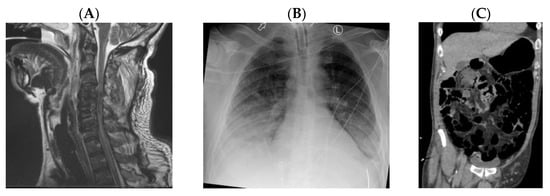

6.1. Case 1

6.2. Case 2